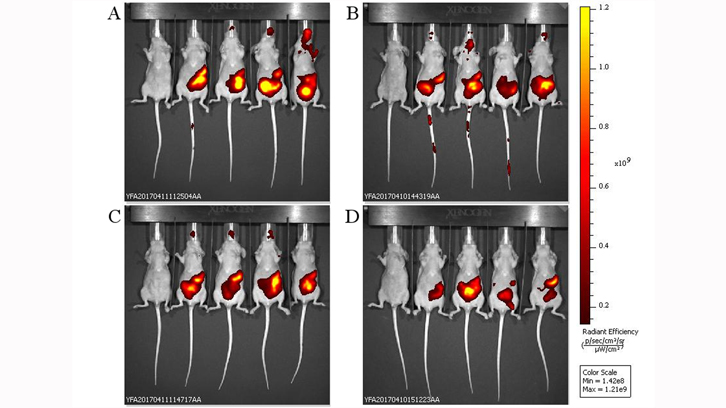

Des de fa un cert temps, s’ha replantejat l’ús de bacteriòfags, els quals són virus que infecten exclusivament als bacteris, com alternativa als antibiòtics o com a mesura complementària....